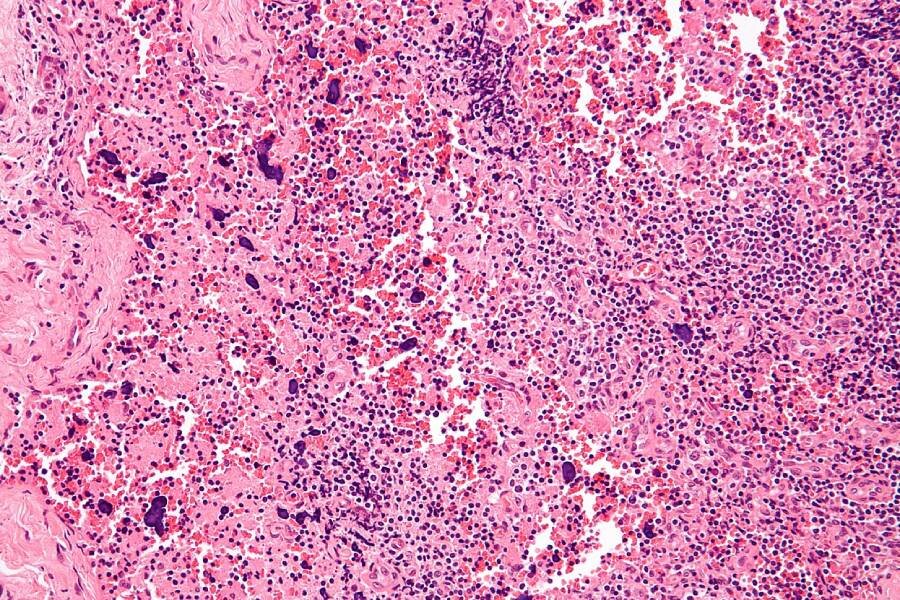

Изменения лимфатического узла, вызванные системной красной волчанкой Фото: wikipedia.org